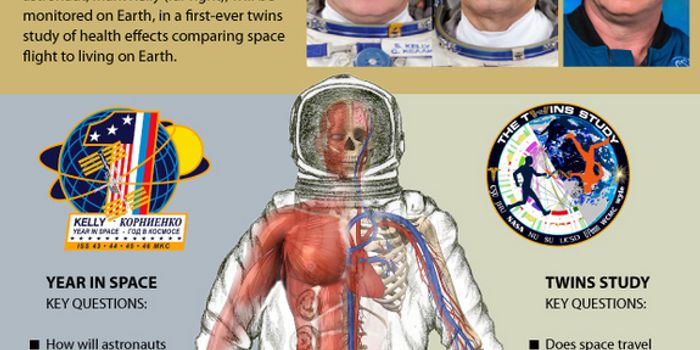

OCT 29, 2017Genetics & GenomicsOver the past year, findings from a Twin Study by NASA have been revealed.

FEB 29, 2016Space & AstronomyAfter a long 340-day stay aboard the International Space Station, NASA astronaut Scott Kelly will be returning to Earth ...